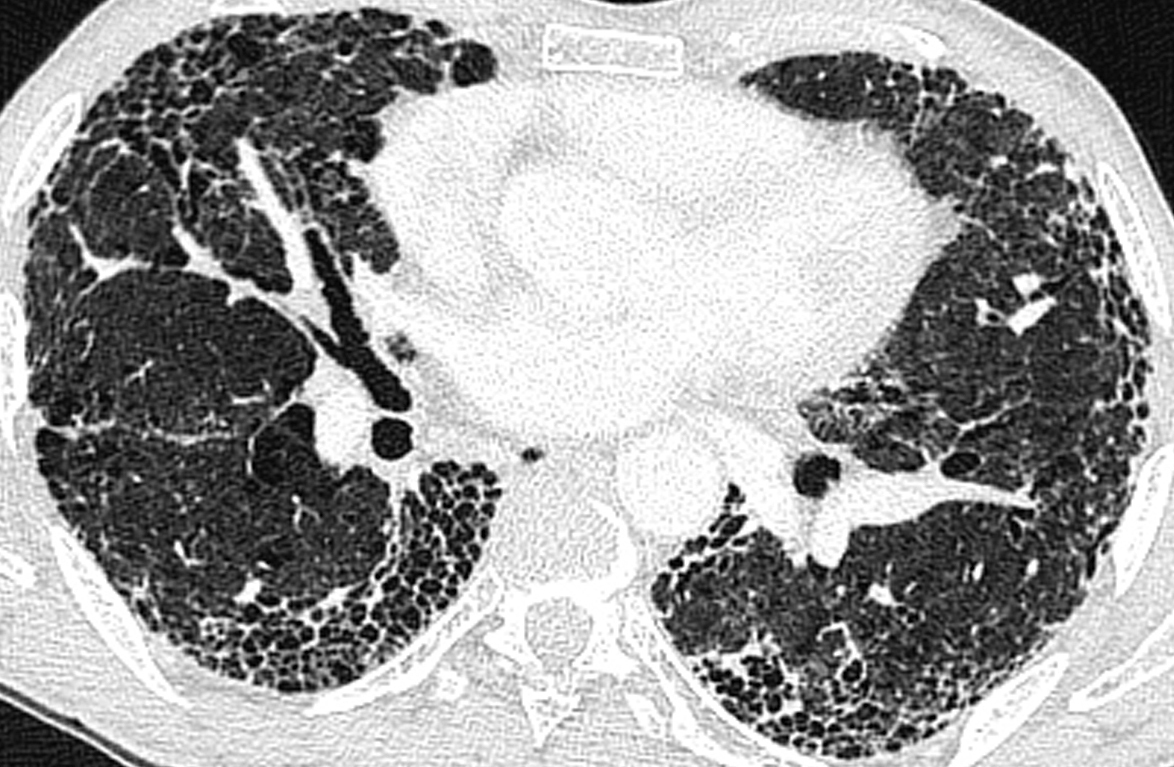

La radiographie de thorax est la suivante :

Question 1 : Qu’est-il possible d’affirmer d’après la radiographie de thorax

Prédominance de réticulations de manière diffuse

Culs de sac pleuraux bien visibles

Absence de cœur en goutte, d’aplatissement des coupoles et d’horizontalisation des côtes

Un syndrome interstitiel est évoqué sur la radiographie thoracique devant la présence de réticulations diffuses majoritairement. Ces traits sont orientés dans toutes les directions, pouvant dessiner ainsi des polygones correspondant aux lobules pulmonaires.

Le syndrome interstitiel radiologique peut être composé de :

- réticulations (« traits » correspondants aux septa lobulaires)

- micronodules (<3 mm)

- épaississements péri-broncho-vasculaires

- verre dépoli